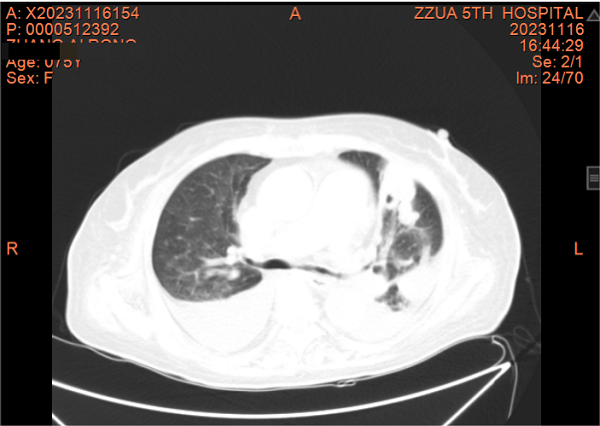

一个月前,张阿姨再发胸闷、心悸,这次张阿姨主动找到了全科医学科。住院期间因受凉出现鼻塞、流涕、发热,病情进展迅速,咳嗽、咳痰、胸闷、心悸、气喘等症状明显加重,动脉血气提示Ⅰ型呼吸衰竭并代谢性酸中毒。张阿姨精神特别差,情绪也十分低落。全科医学科主任刘培杰主任医师及别柏林主治医师综合分析病情后,第一时间给予碳青霉烯类积极抗感染、糖皮质激素抗炎、硝酸酯类扩张血管减轻心脏负荷、控制快速心室率、经鼻高流量湿化氧疗等综合治疗,护理团队给予饮食指导及心理辅导,张阿姨的病情很快得到控制,经复查胸部CT,肺部病变较前明显吸收,出院时再次对其慢性病管理及预防、治疗措施对其进行了再次的细致交代,病情好转出院。